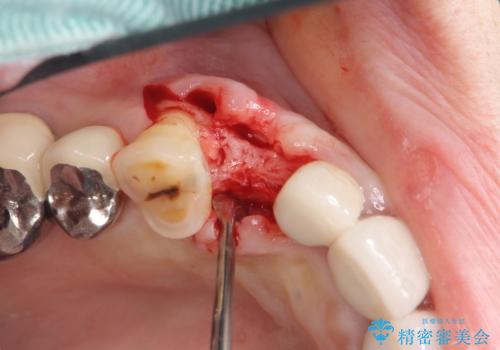

クラウン下に再発した深い虫歯 インプラントによる機能回復

- 定期検診で通院されていたところ、20年前に他院で治療した前歯のセラミック歯の下に深い虫歯が再発していることがわかりました。

ブリッジや歯の挺出を行い保存する提案も行いましたが、短期間の定期的な通院が難しくインプラントによる少ない回数での治療を希望されました。